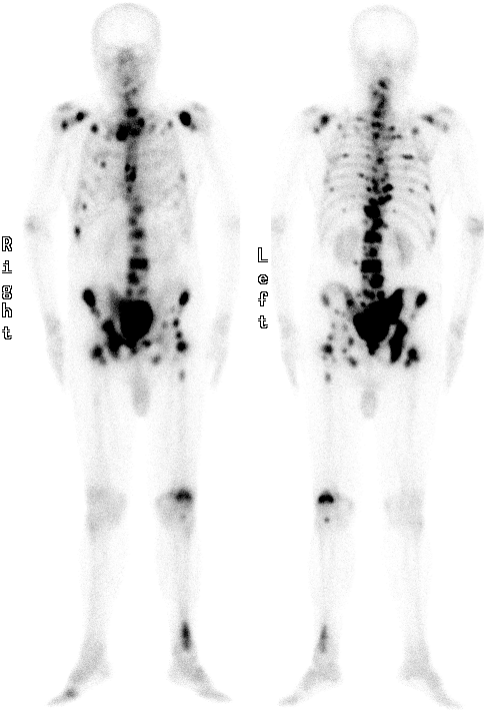

病例一:甲状腺癌骨转移

甲状腺显像表现为左叶“冷”结节;甲状腺切除手术后病理甲状腺乳头状癌,行131I甲状腺癌转移灶全身显像(右图),示第5腰椎异常浓聚131I、部分甲状腺残余组织。